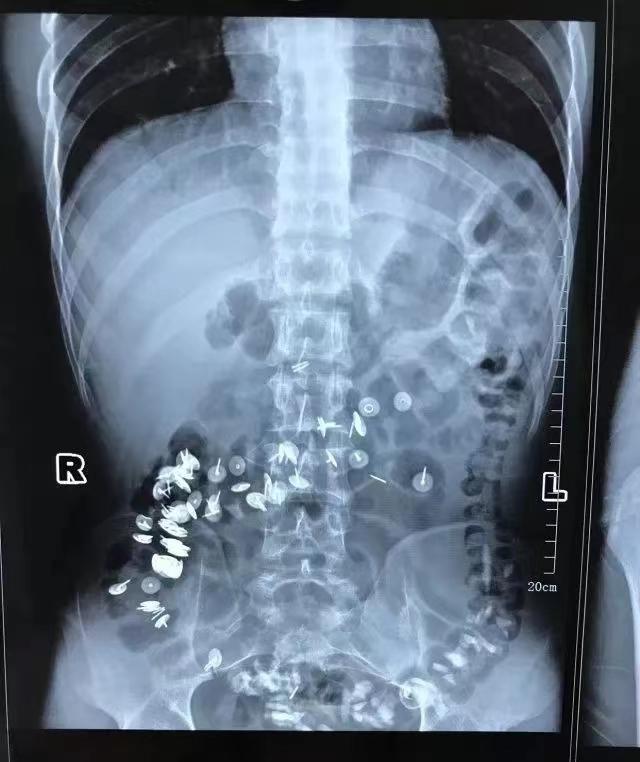

除了从肛门塞进体内的异物外,还有从嘴里吞入奇奇怪怪的异物的案例:就比如有患者有异食癖,在吞入玻璃后,又吞入了图钉...

(图片:图钉位置示意图1)

片子中可以看到,肠道内密密麻麻布满了图钉,超级恐怖!

小看看到这个片子的时候鸡皮疙瘩都起来了...

(图片:图钉位置示意图2)

幸运的是,数百颗图钉在消化道里都没有造成胃肠道穿孔。

经过保守治疗后患者基本恢复正常。